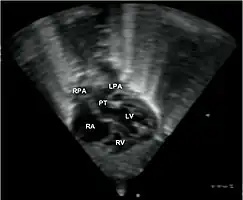

Echocardiogram: An echocardiogram is an ultrasound of the heart which accurately assesses the heart’s structure and function, and can show the specific features of TGA, if present. This imaging modality allows for the definitive diagnosis of TGA to be made. [8]

Echocardiogram in transposition of the great arteries. This subcostal view shows the left ventricle giving rise to a vessel that bifurcates, which is thus identified as the pulmonary artery.

Abbreviations: RA=right atrium, RV=right ventricle, LV=left ventricle, PT=pulmonary trunk, LPA and RPA=left and right pulmonary artery.